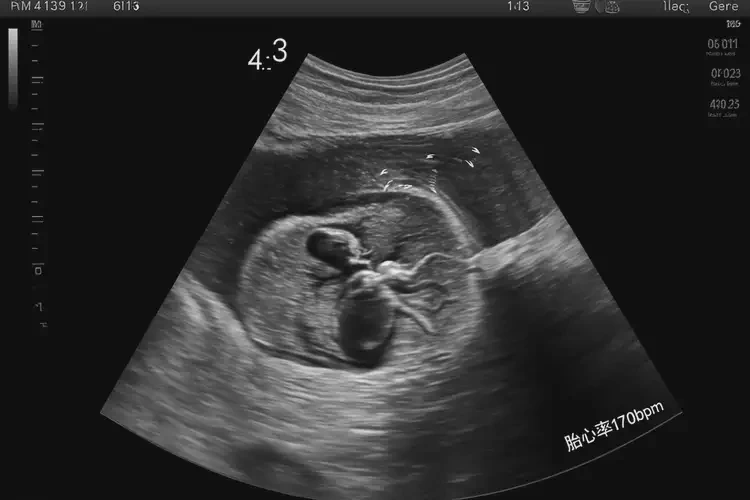

孕4周3天胎心170多寶寶還能要嗎

胎心率在170次/分鐘是正常范圍,寶寶可以要。

胎心率是指胎兒心臟每分鐘跳動的次數(shù),通常在孕4周時,胎心率在140-170次/分鐘之間被認為是正常范圍。胎心率在170次/分鐘是正?,F(xiàn)象,并不意味著寶寶有問題,可以繼續(xù)妊娠。

孕4周3天胎心170多寶寶還能要嗎(圖1)